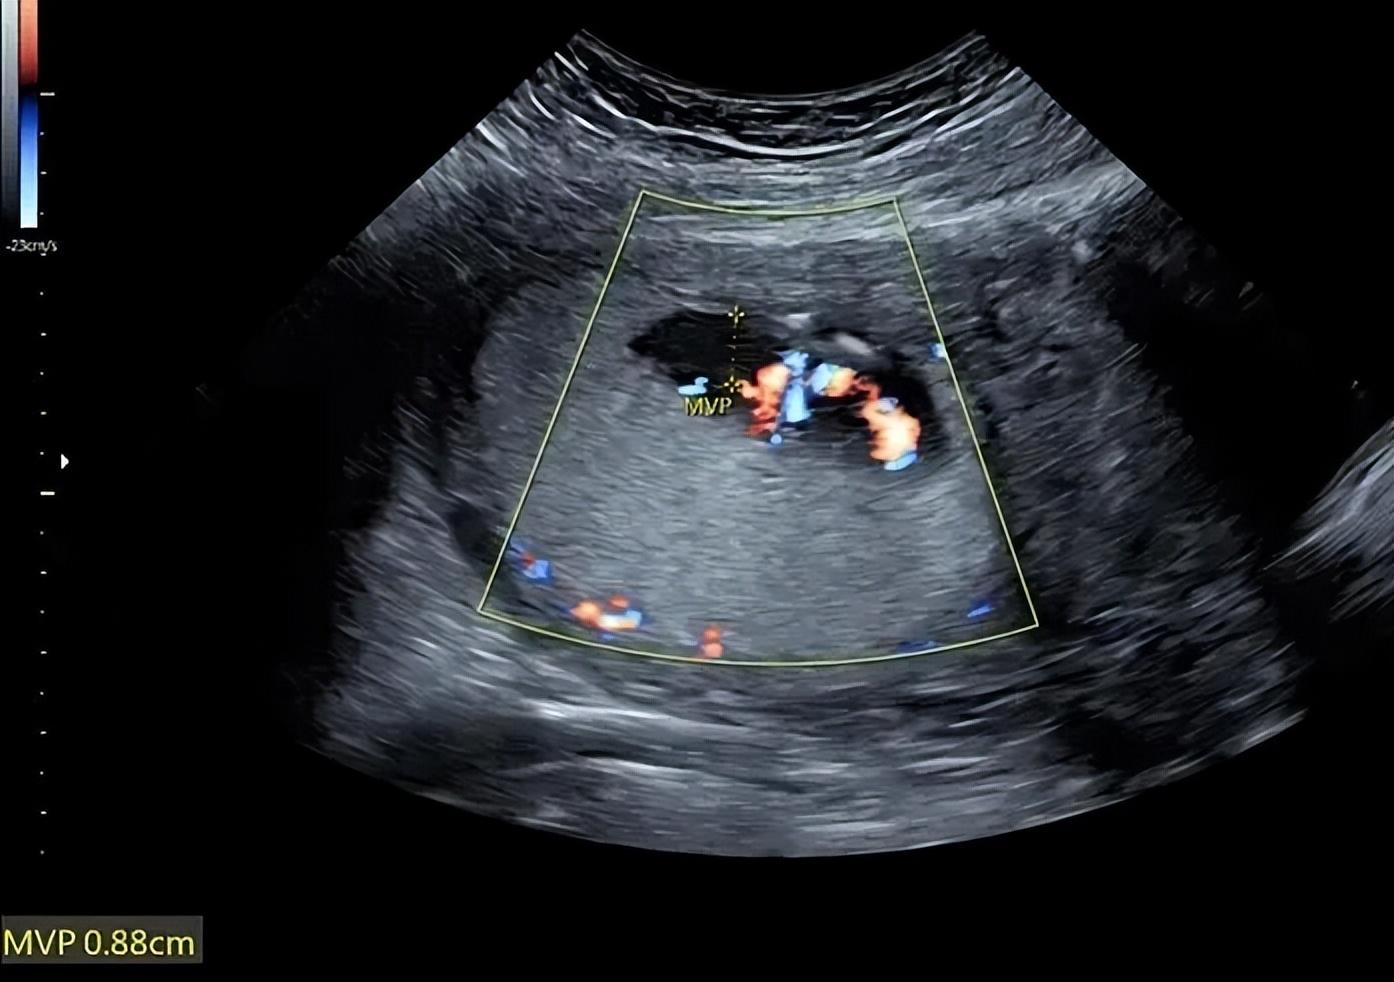

医生检查发现这就是羊水,腹部超声显示羊水最大深度仅为0.9厘米,诊断为羊水过少。

三天后她回医院复查,并且带来了好消息,羊水不再渗出了,最大羊水深度已经改善至1.67厘米。